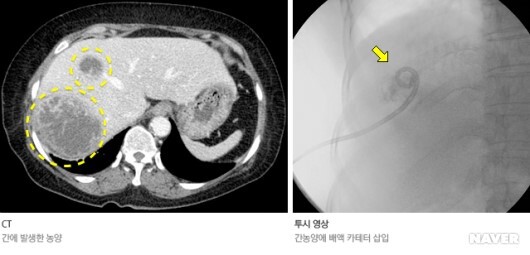

Percutaneous abscess drainage 경피적 농양 배액술

간농양 Liver abcess 내의 drain tube 삽입이나 기타 수술 후의 fluid collection 등 Non vascular에 이용되는 모든 튜브 배액을 PCD 라고 한다.

항생제로도 농양의 치료가 충분하지 못할 경우 PCD를 시행한다.